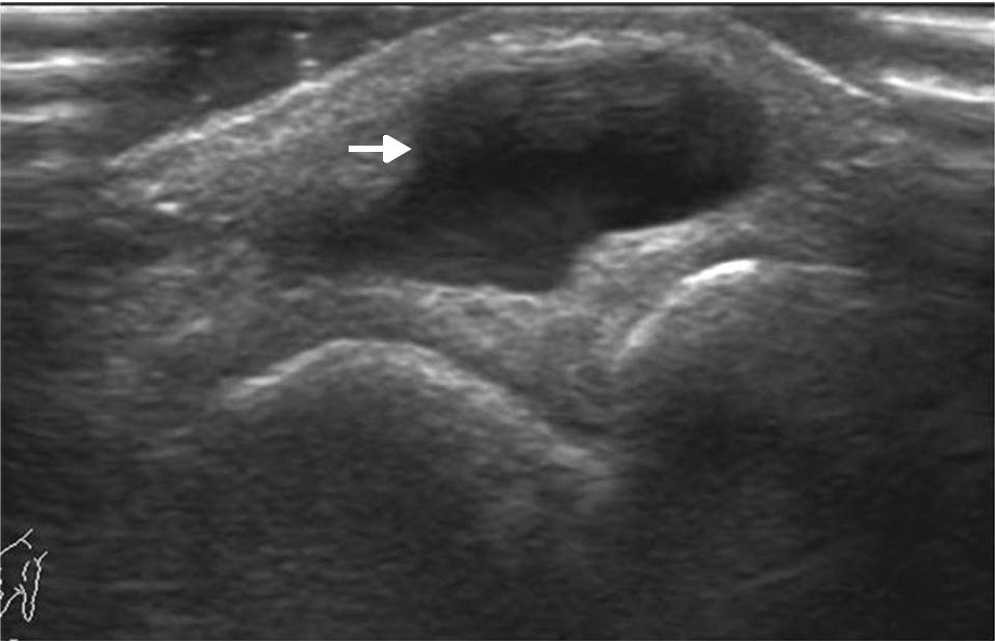

La ecograf??a es el m??todo ideal para la exploraci??n del sistema musculoesquel??tico, en tanto brinda la posibilidad de evaluarlo en reposo o en movimiento, observando los cambios en tiempo real. Adem??s, permite la comparaci??n del sitio exacto del dolor con su lado contralateral, adquiriendo im??genes en panor??mica19.

Los actuales transductores de alta frecuencia (12-18 MHz) tienen excelente resoluci??n para analizar las estructuras superficiales (m??sculos, tendones, ligamentos y bursas) y sus patolog??as20 (figs. 14 y 15). La ecograf??a en escala de grises permite una gran imagen anat??mica de la lesi??n, mientras que el Doppler color identifica la vascularizaci??n del tejido y las im??genes panor??micas otorgan una visualizaci??n extensa del campo de visi??n, que muestra la lesi??n y su relaci??n con las estructuras vecinas (fig. 16).